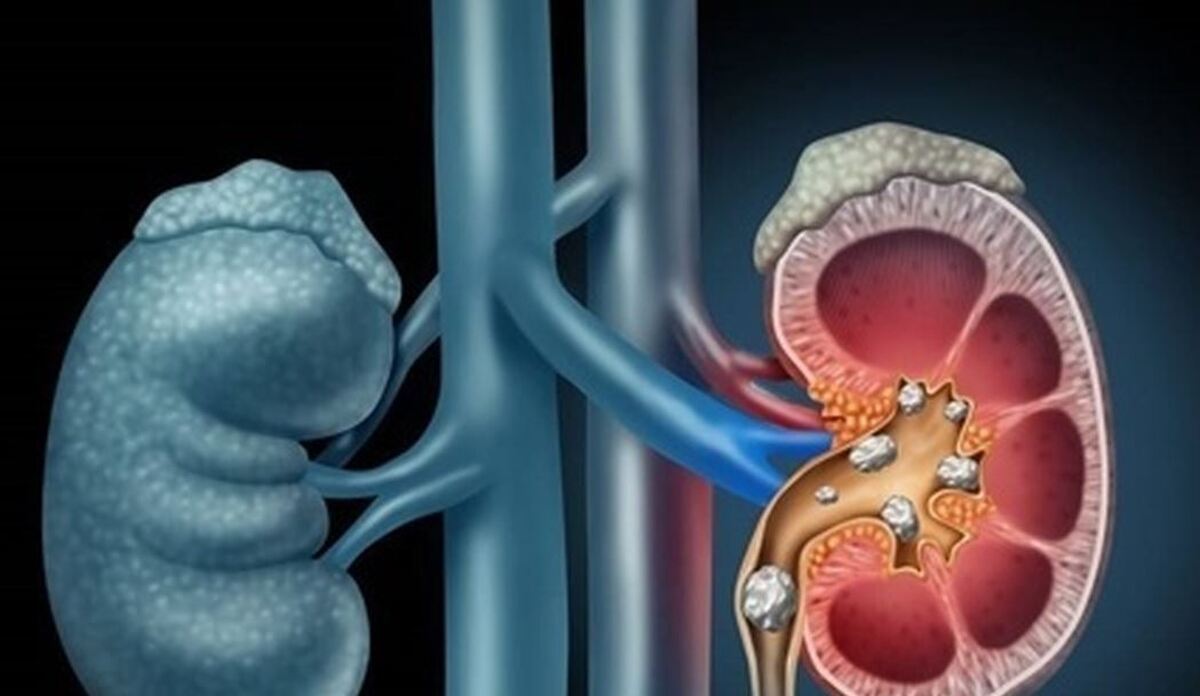

بیماری سرطان یا نارسایی کلیه با چه نشانههایی بروز پیدا میکند؟

به گزارش مجله خبری نگار،دکتر رسول جعفری با اشاره به اینکه تکرر ادرار بیش از حد میتواند نشانهای از اختلالات دستگاه ادراری باشد، افزود: ادرار کردن ۵ تا ۶ بار در طول روز طبیعی است، ولی اگر این تعداد بیشتر شود، بهویژه در شب، باید جدی گرفته شود.

وی با اشاره به نشانههای خطرناک که نیازمند مراجعه سریع به پزشک است، گفت: علائمی مانند، سوزش یا تکرر ادرار، احساس فوریت در ادرار، وجود خون در ادرار (چه آشکار و چه فقط در آزمایش)، درد پهلو همراه با تب و کاهش وزن، لمس توده یا ترشحات مجرا، باید جدی گرفته شوند.

دکتر جعفری تأکید کرد: عفونتهای ادراری طیف وسیعی از عفونتهای کلیه، مثانه و پروستات را شامل میشوند و در صورت درمان ناقص یا مصرف خودسرانه آنتیبیوتیک، ممکن است مزمن یا مقاوم شوند.

وی با بیان اینکه مصرف آب بهویژه در فصل تابستان کلید پیشگیری از سنگهای کلیه است، گفت: افراد باید روزانه بین ۲ تا ۳ لیتر آب بنوشند و مصرف نمک، قند و مواد پروتئینی را کاهش دهند، بهویژه در مناطق گرم و خشک.

به گفته دکتر جعفری، مصرف سیگار و استفاده طولانیمدت از مسکنها نیز از عوامل شناختهشده در بروز سرطان مثانه و کلیه هستند و به مرور عملکرد کلیه را مختل میکنند.